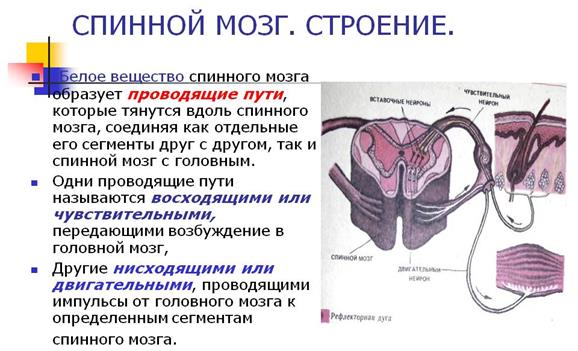

Спинной мозг и двигательная активность: Важные аспекты